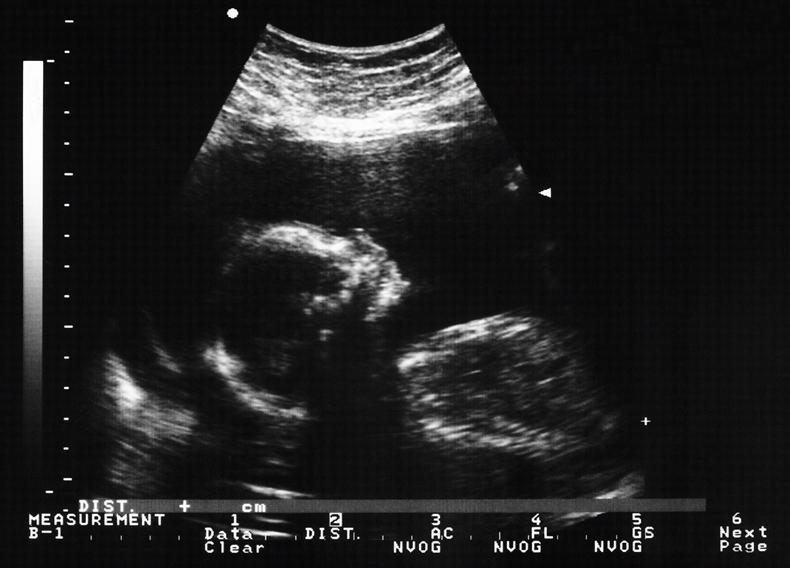

Anomaly scans can diagnose serious conditions and fatal fetal abnormalities which allow health professionals to help manage medical conditions for both mother and baby.